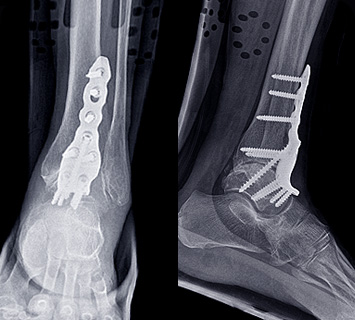

발목교정술

발목고정술